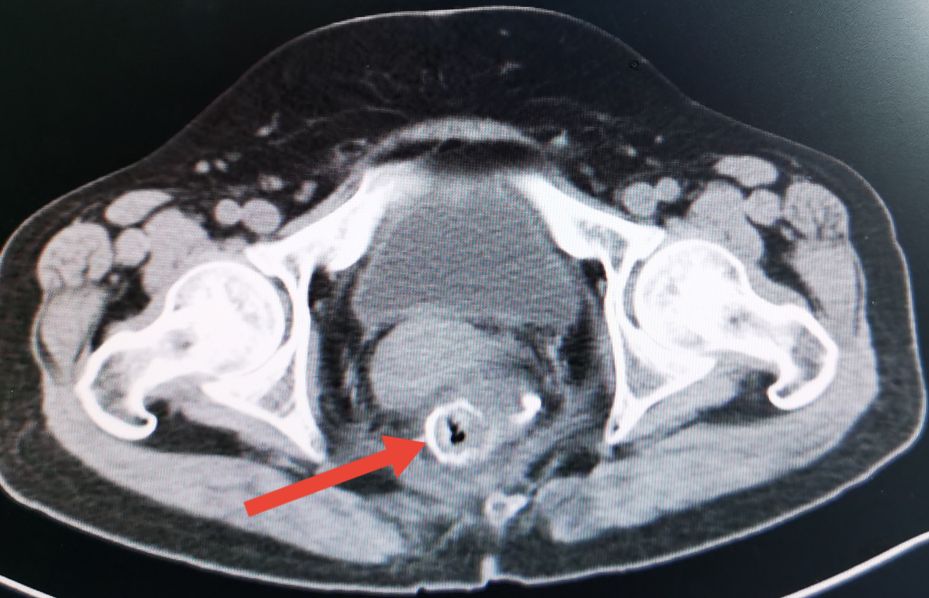

直肠癌术后吻合口狭窄的CT表现